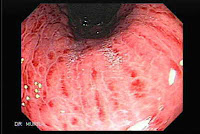

Gastritis adalah peradangan lokal atau menyebar pada

mukosa lambung yang berkembang apabila mekanisme protektif mukosa di penuhi

Gastritis adalah suatu peradangan mukosa lambung yang

dapat bersifat akut, kronik, difusi atau lokal (Silvia,1995:251) Gastritis